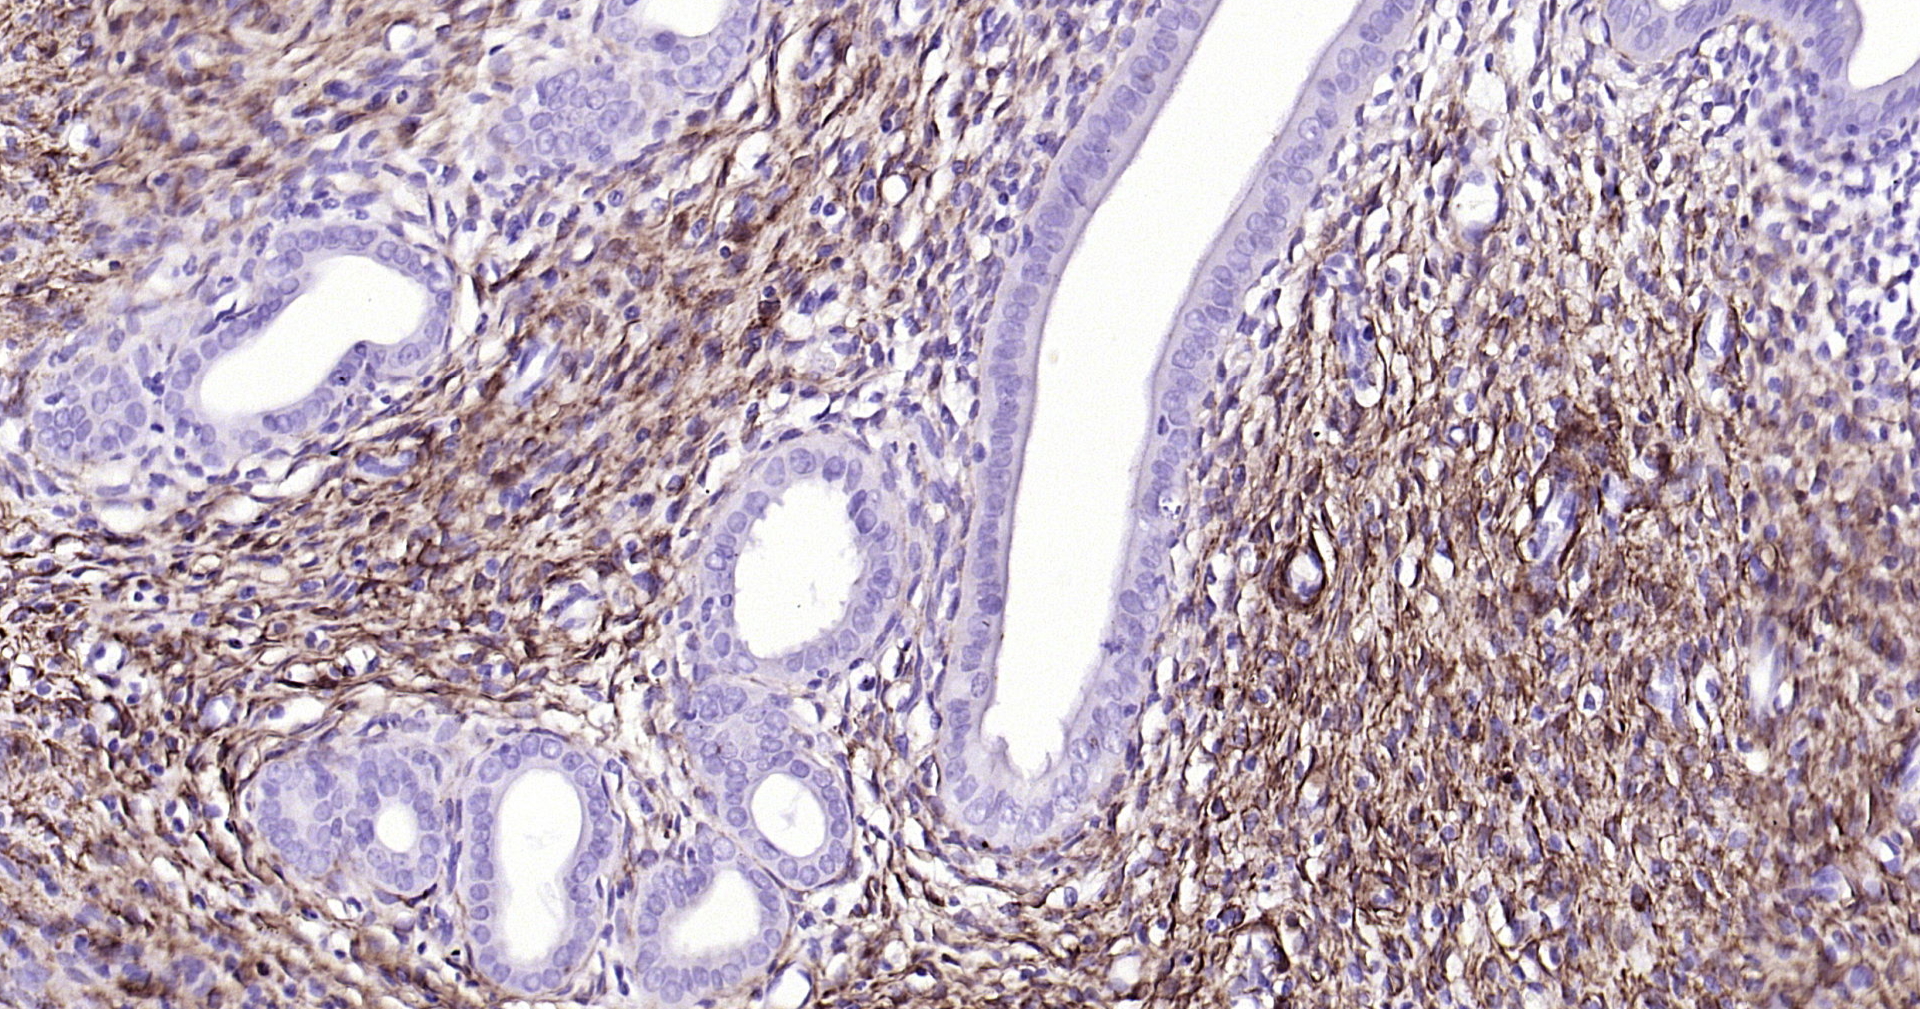

• IHC-P

IHC-P 1:100-500